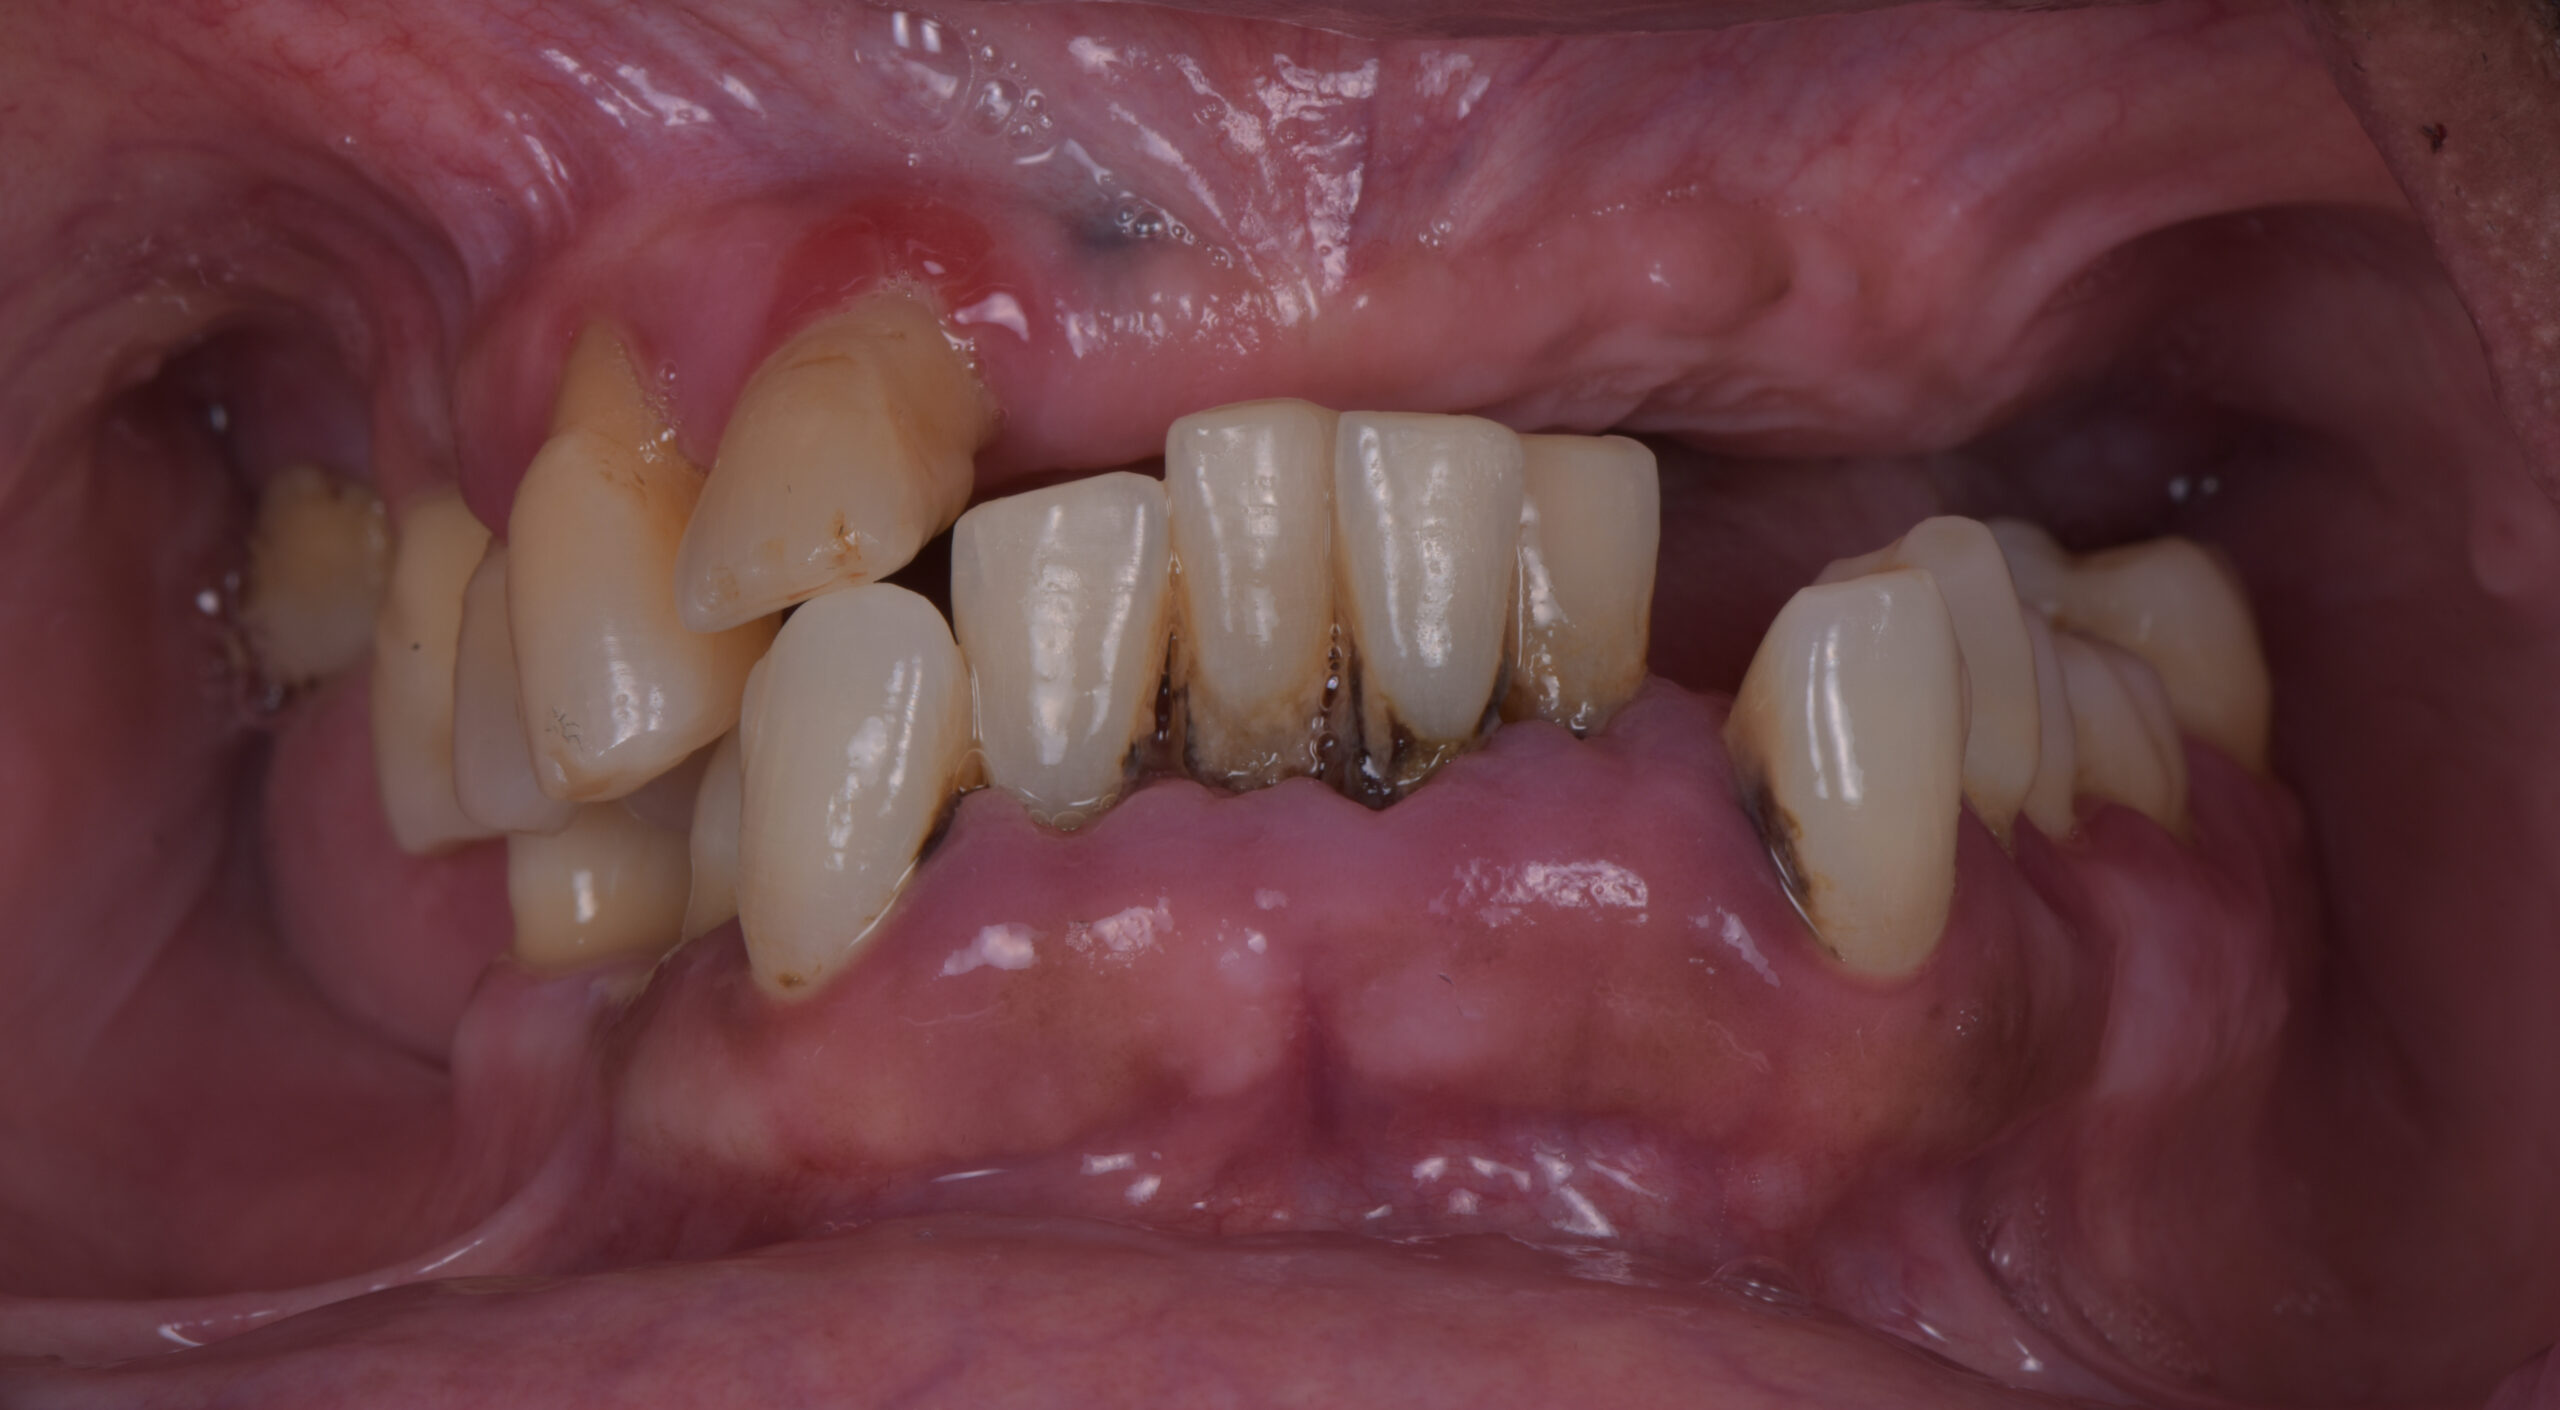

名古屋で歯がボロボロでも、全部抜くとは限りません

名古屋で歯がボロボロになったとき、最初に整理したいのは、「残せる歯があるか」ではなく、「残した結果、口全体が長く機能するか」です。

特に、歯がボロボロ、名古屋で歯を全部治したい、多数歯欠損という状況の方は、虫歯、歯周病、欠損、かみ合わせの崩れが同時に進んでいることが少なくありません。

この段階では、残せる歯が数本あっても、口全体の寿命を考えると、抜歯を含めた再建の方が合理的な場合があります。

一方で、見た目が悪くても、すぐに名古屋 オールオン4や総抜歯が必要とは限りません。

まずは、保存できる歯と、保存すると全体の寿命を縮める歯を分けて考えることが出発点です。